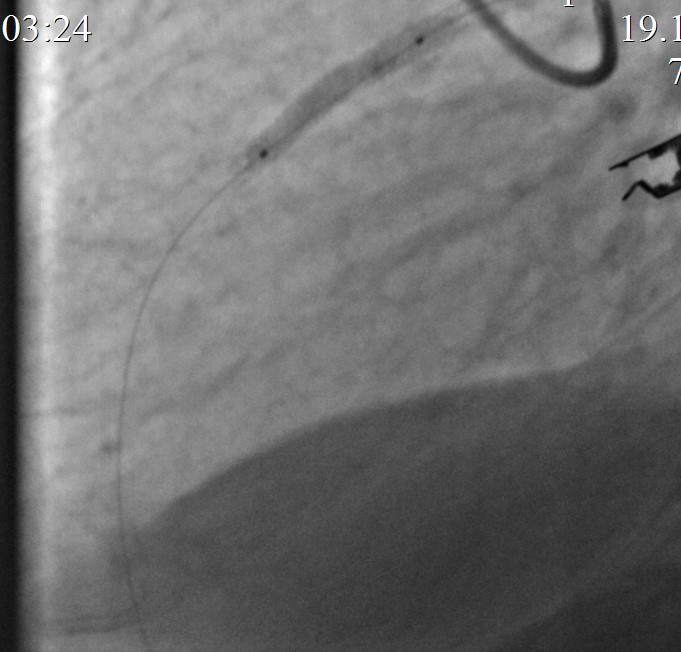

Контрольная КАГ: среднем отделе выраженная экстравазация контраста, (III тип по Ellis – в анатомическую полость).

Произведено временное перекрытие («пломбирование») просвета ПМЖВ « выше зоны стентирования» баллонным катетером 3,5х24,0мм при Р до 6 атм. (10мин). Подготовка к экстренному стентированию «стент-графтом».